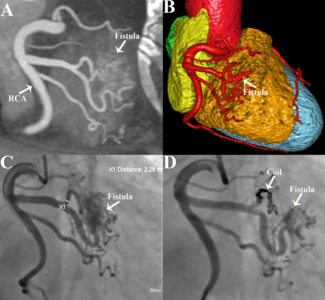

Leizhi Ku, MD; Yuhang Wang, MD; Zheng Liu, MD; Xiaojing Ma, PhD

The authors highlight the role of coronary computed tomography angiography and coronary angiography in diagnosing and treating congenital coronary artery-right ventricular multiple microfistulas.